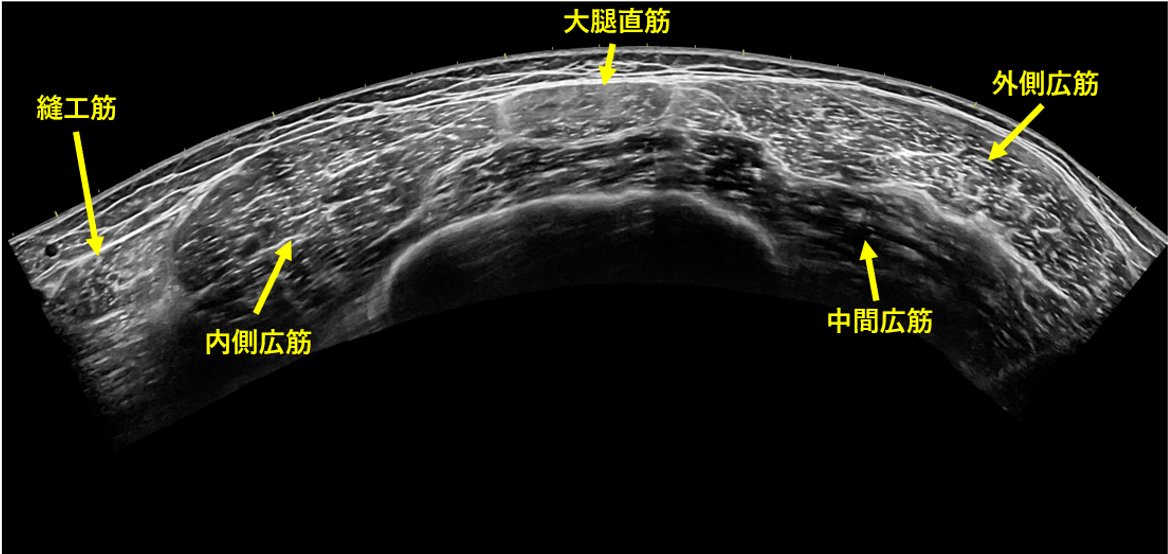

大腿前面の解剖も一緒にどうぞ

私の中では、大腿直筋が縫工筋と筋膜張筋の深層へ綺麗に入り込むところが好きです

横断エコー画像を撮影してみると色々考えが深まる! 例えば ①縫工筋の膜が内側広筋の膜と連続していたり ②中間広筋が内側広筋の下に潜り込んでいたり ③外側広筋と中間広筋の連続性があり、それぞれどこまで影響を及ぼしていたり... いろいろ撮影してみよう!!!pic.twitter.com/ODGWAJR9NE